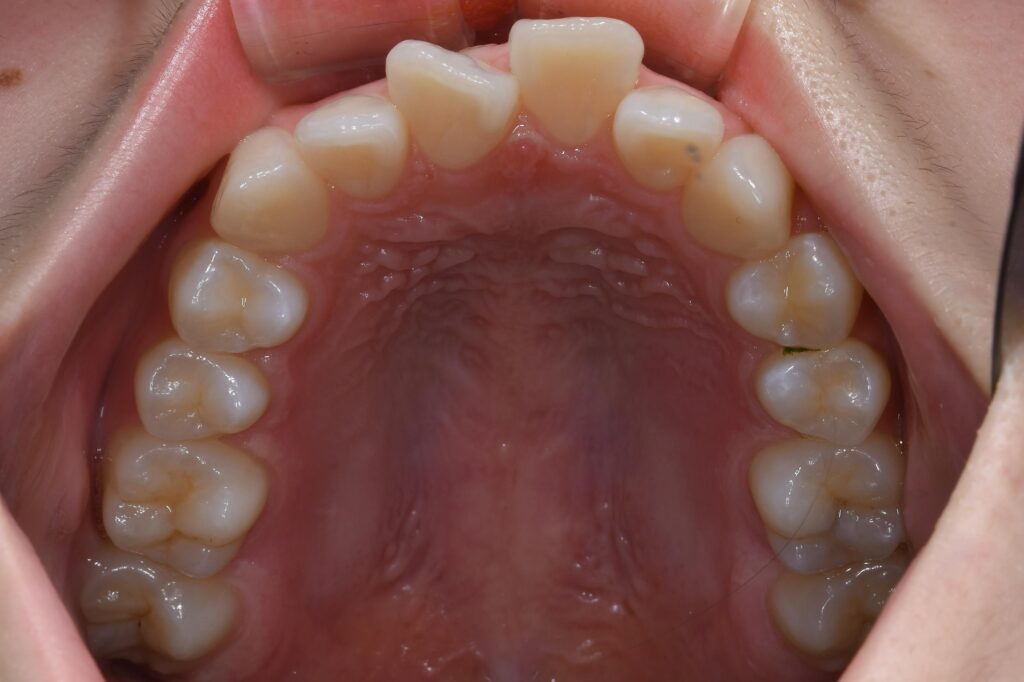

まずは術前の状態をお見せ致します。

【矯正治療前】

いかがでしょうか。

この患者様のお悩みは出っ歯。横からの写真で、出具合が顕著に確認できます。

治療計画として小臼歯を抜歯して歯を並べることにしました。